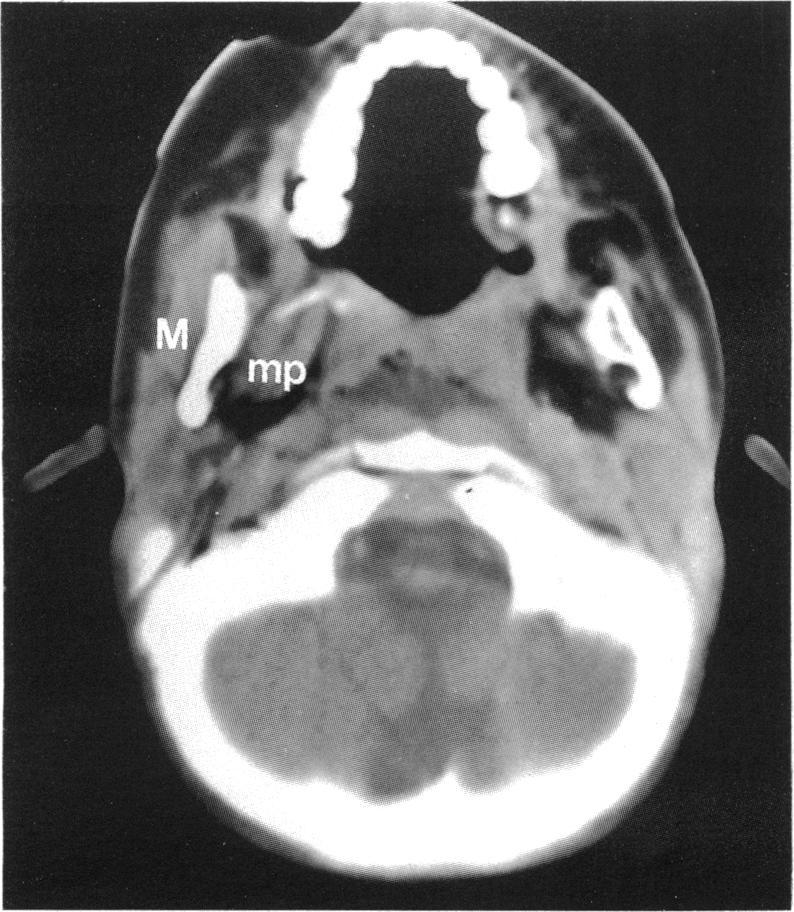

Neurotrophic keratitis presenting in infancy with involvement of the motor component of the trigeminal nerve.

Br J Ophthalmol. 1993 Oct;77(10):679-80. doi: 10.1136/bjo.77.10.679.

Trigeminal neuropathy: improved imaging with a dental computed tomography software program.三叉神经病变:使用牙科计算机断层扫描软件程序改善成像

The normal and diseased masticator space.正常和病变的咀嚼肌间隙。

A CT-clinical approach to patients with symptoms related to the V, VII, IX-XII cranial nerves and cervical sympathetics.针对有与第V、VII、IX - XII颅神经及颈交感神经相关症状患者的CT临床诊疗方法。